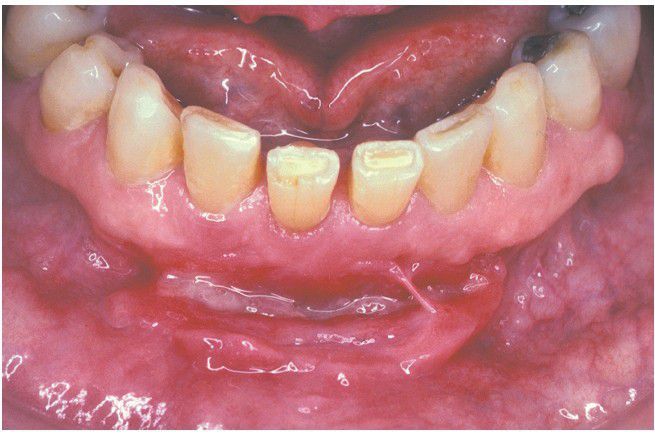

Crohn Disease.

This patient has a linear ulceration of the mandibular vestibule. An adhesion between the alveolar and labial mucosae was caused by repeated ulceration and healing of the mucosa at this site.